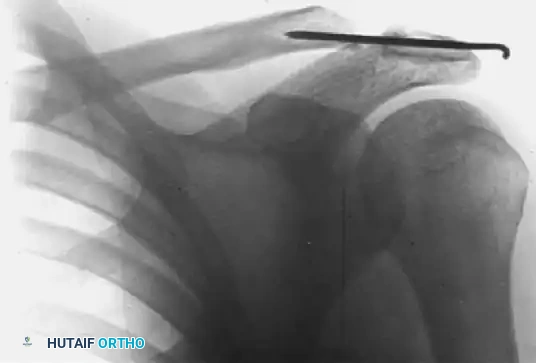

FIGURE 2: Stewart technique. (B) Six weeks after surgery, demonstrating transacromial K-wire fixation maintaining anatomic reduction.